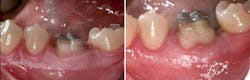

In my opinion, the crown lengthening should be done after the root canal treatment has been completed. There are several reasons for this. One is that, in most cases, a root canal treatment determines the ultimate salvageability of the tooth and whether a proper restoration can be placed without compromising the integrity of the tooth. The second reason is the ease of treatment. Once crown lengthening is performed, due to the nature of the treatment and the amount of involvement with hard and soft tissues, it takes up to 10 weeks to achieve ideal healing before any additional stress—such as placing a rubber dam clamp on the tooth or having the patient stretch his or her cheeks open for long periods of time—can be applied to the tooth or surrounding structures. This type of delay in root canal treatment of a compromised tooth can potentially lead to complete failure of the tooth and further trauma from bacterial invasion or destruction of tooth structure under normal wear and tear. Another factor to consider is that by doing root canal treatment after crown lengthening, the newly formed Sharpey’s fibers and connective-tissue attachment can come under a tremendous amount of stress from the rubber dam clamp, especially in situations where there is no distal adjacent tooth to use as a clamp anchor. This type of stress can lead to further damage of the newly formed periodontal ligament (PDL) and connective tissues. (figure 3)